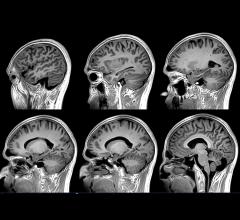

Information from brain magnetic resonance images (MRIs) can help identify people with attention deficit hyperactivity disorder (ADHD) and distinguish among subtypes of the condition, according to a study appearing online in the journal Radiology.